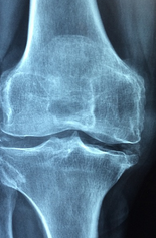

무릎 관절은 무릎을 이루는 뼈인 대퇴골, 슨골, 장골이 연결되어 이루어진 관절로, 운동과 일상 생활에서 매우 중요한 역할을 합니다. 무릎 관절은 뼈뿐만 아니라 연골, 인대, 근육, 힘줄 등 다양한 조직으로 이루어져 있습니다. 이러한 구조는 무릎의 안정성을 유지하고, 충격을 흡수하여 무릎 관절 부상을 방지하는 역할을 합니다. 그러나 연령이나 외상, 과부하 등에 의해 무릎 관절을 포함한 구조에 손상이 발생하면, 통증, 부종, 운동 불편 등의 증상을 유발할 수 있습니다. 따라서 무릎 관절을 건강하게 유지하기 위해서는 적절한 운동, 체중 조절, 안전한 운동 방법 등을 실천하여 무릎 관절 부상을 예방해야 합니다. 무릎 관절에 문제가 있을 경우에는 적절한 치료와 관리를 받아 빠르게 회복할 수 있습니다.